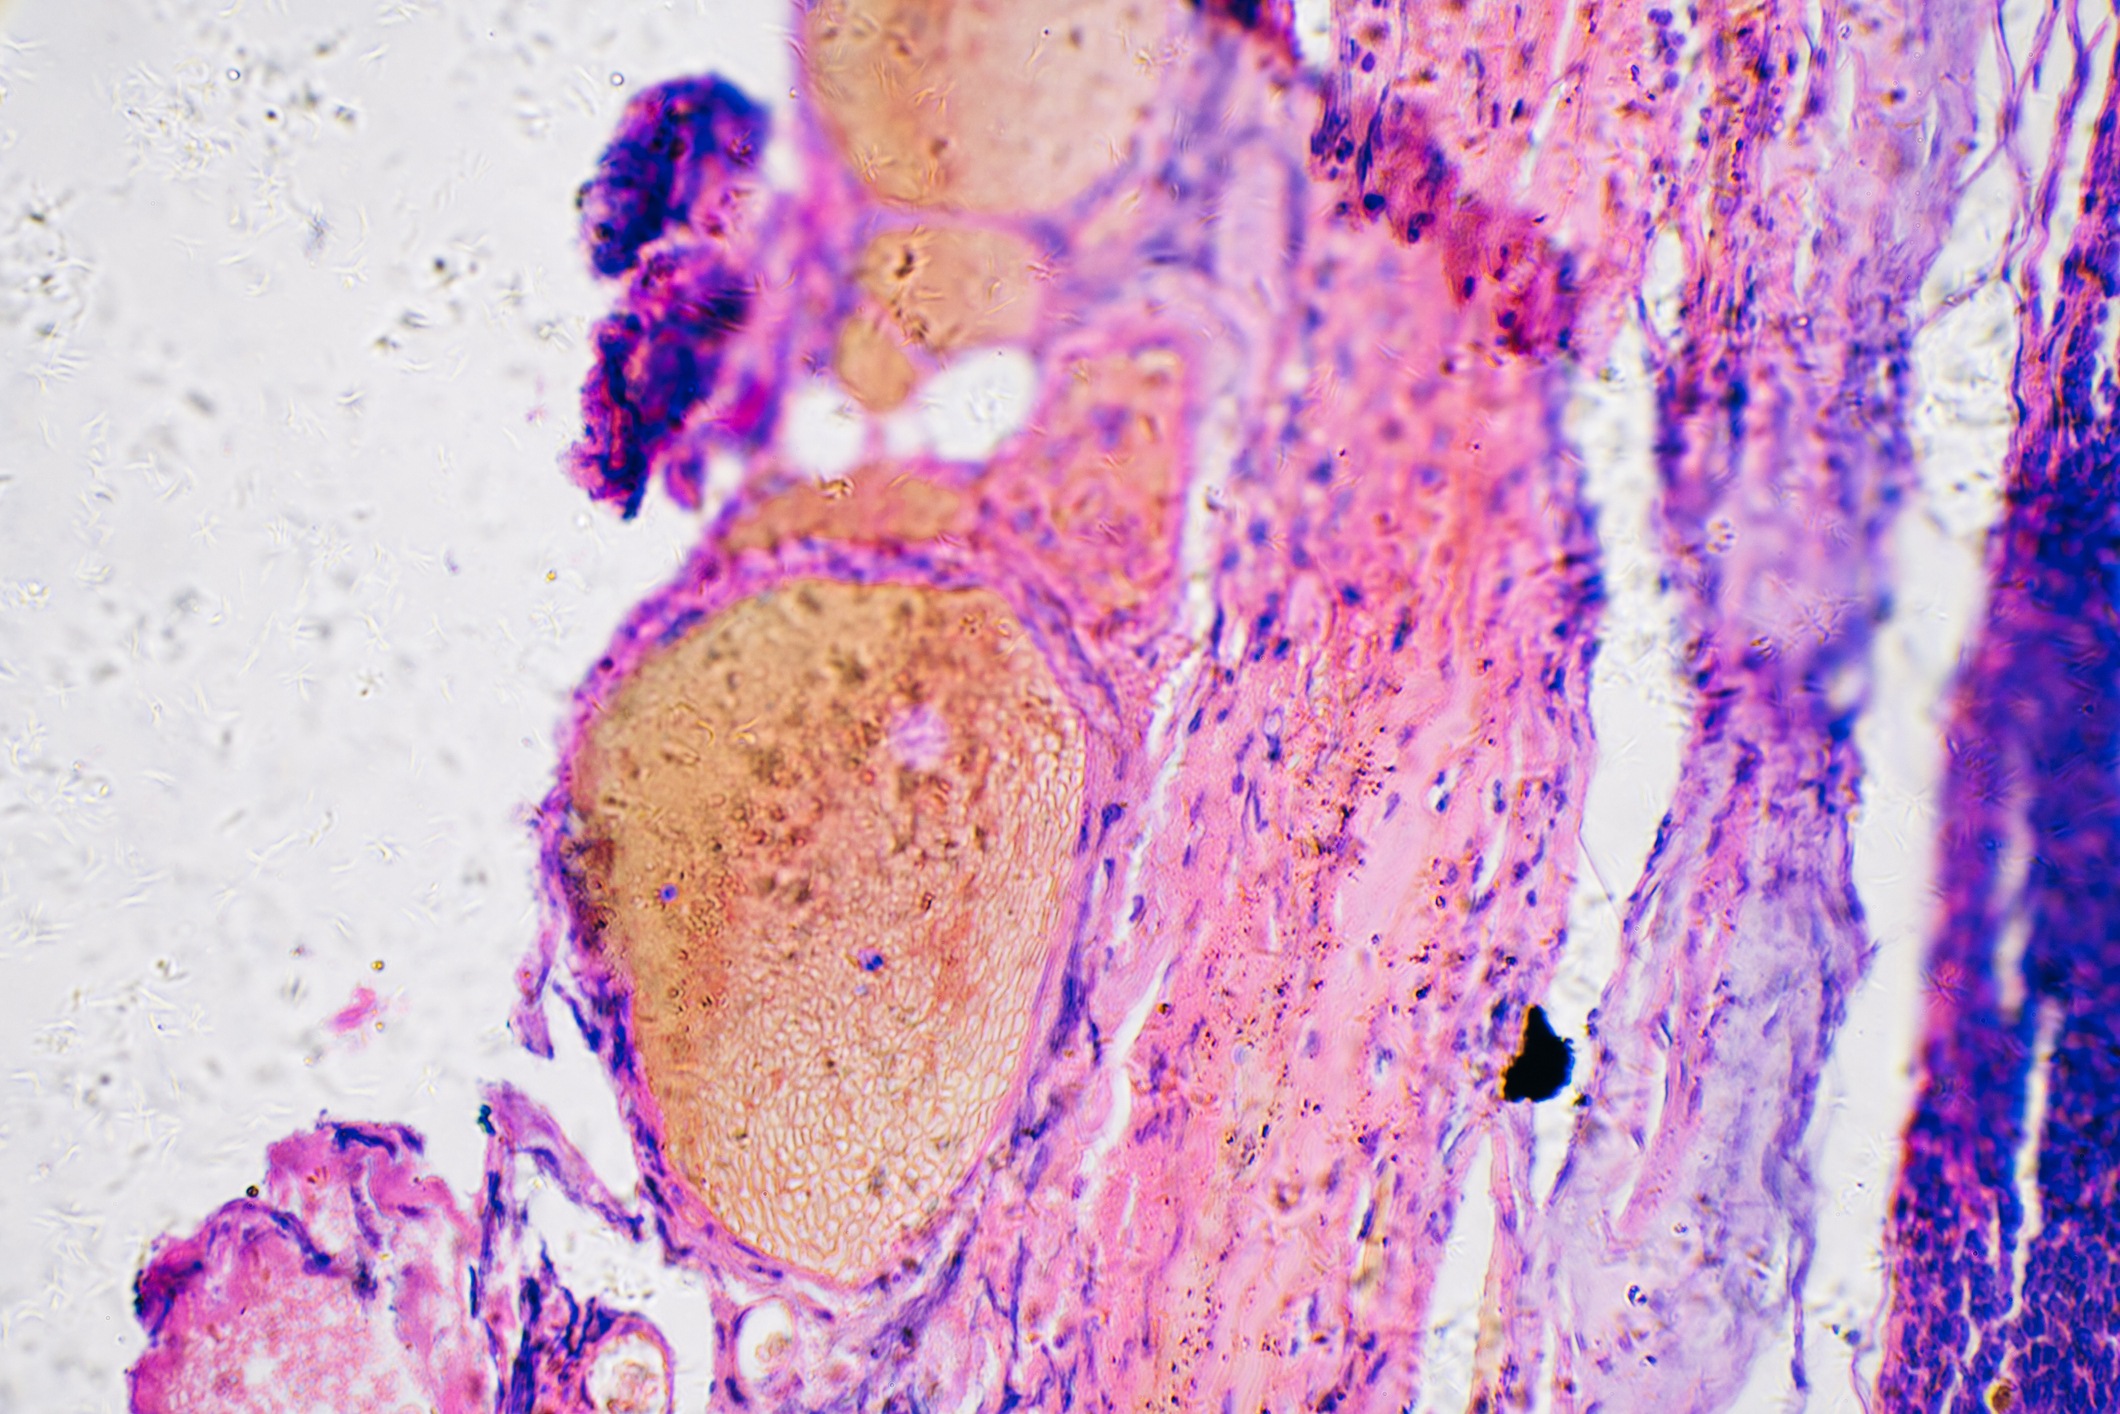

Chromosomes are the structures containing our DNA. Inside each of our cells, our DNA is divided into 46 of these structures, 23 near-identical pairs from each of our parents. Together, all the chromosomes contain the entire recipe for making us. They encode the information that controls the cells. This information is obviously very valuable and needs to be protected. Cells host billions of chemical reactions and are constantly exposed to many potentially harmful outside forces. The ends of each chromosome are especially vulnerable to damage, just as a shoelace without an aglet will unravel beginning at the tip. Our cells solve this problem by adding sequences of non-important DNA to the ends of each chromosome. This DNA only serves as protection and can be lost without any harm being done. It just sits there so that valuable DNA does not.

Each time our cells divide, they lose a little bit of telomere.[13] Some cells, such as stem cells, can use the enzyme telomerase to replace the lost telomere. However, most normal cells cannot. This means most cells can only divide a certain amount of times (40-60) before they start running out of telomere and reach Hayflick’s Limit.[14]